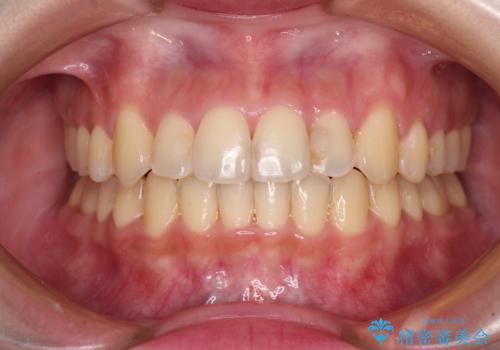

できる限り短い期間で終えたい ワイヤー矯正による咬み合わせの改善

- 前歯のデコボコを気にして来院された患者様です。

上顎右側犬歯が八重歯になっており、それによって奥歯が前方に移動しているため、右側の咬み合わせの改善が必要と判断されました。

より治療を速やかに行うため、上顎右側にアンカースクリューを使用し、目標としていた1年半ほどで治療を終えることができました。